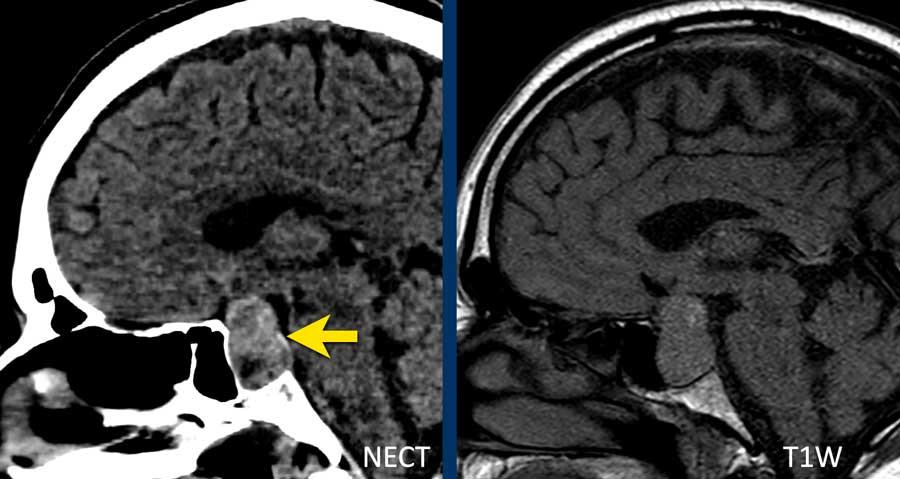

Bệnh nhân này nhập viện với hình ảnh khối máu tụ tiểu não.

Tiếp tục xem hình ảnh chuỗi xung T1W…

Chuỗi xung T1W cho thấy ổ xuất huyết tăng tín hiệu (mũi tên).

Xuất huyết nội sọ do tăng huyết áp cùng với CAA chiếm 80% nguyên nhân gây khối máu tụ trong nhu mô não.

Cần nghĩ đến CAA khi phát hiện nhiều ổ xuất huyết ngoại vi hoặc xuất huyết thùy ở bệnh nhân cao tuổi.